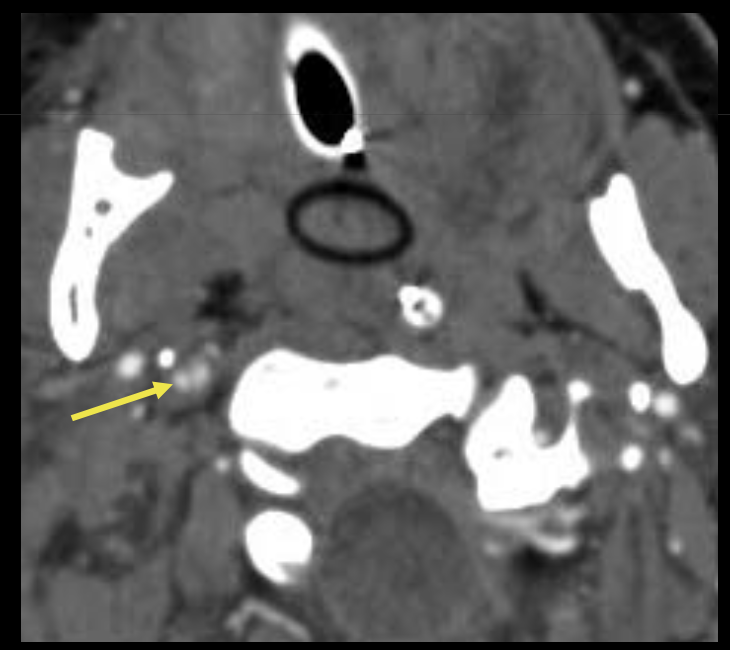

Que regarde-t-on ?

Une dissection vértébrale avec fracture du canal vertébral associé